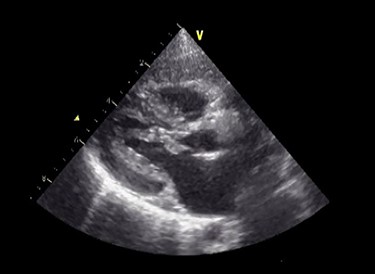

Postoperative echocardiography. The abnormal muscle band has disappeared, and the SAM of mitral valve is well controlled.

Under general anesthesia, cardiopulmonary bypass was established by ascending aortic and bicaval cannulation. After transverse aortotomy, LVOT was exposed through the aortic valve by retracting the aortic wall. The cardiac muscle hypertrophy with abnormal bundle-like cardiac muscle was observed in the LVOT, including the septal area. The hypertrophied area was scooped up by a nerve hook and cut by scalpel (Fig. 2 and Video 2). Next, the left atrium was incised and the mitral valve was exposed. The edge-to-edge technique with a suture of the A2–P2 area was performed for mitral valve reconstruction. Postoperative recovery was uneventful, and echocardiography revealed improved LVOTS with 1.7-m/s peak velocity and no MR or mitral stenosis (Fig. 3 and Video 3).